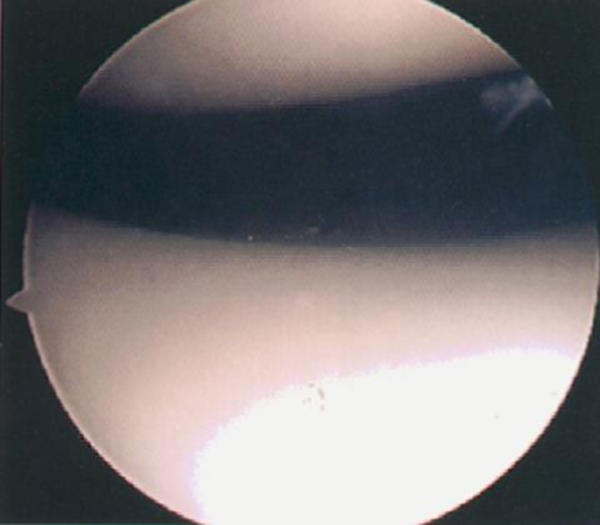

关节镜下髌骨软化症0级表现

Ⅰ级:关节软骨失去珍珠样外观而变得较暗淡,局部软化,肿胀区或纤毛化区的直径<0.5cm。